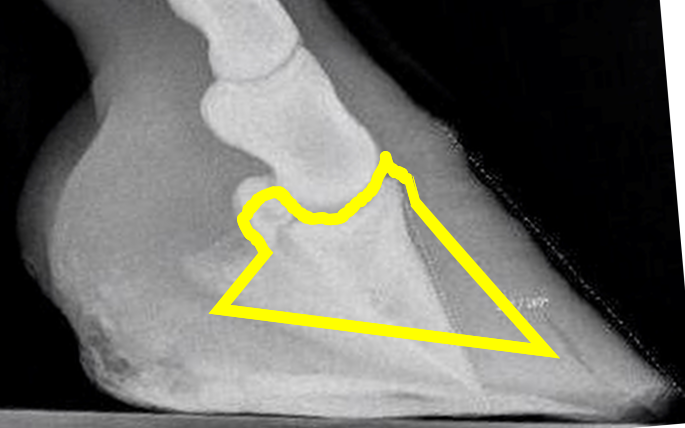

It is not this extreme on all laminitic hooves, but it is too common to neglect. Let me show you another one. If the front of the coffin bone had the same angle as the toe wall before the alleged rotation, it would have been placed as the yellow marking shows.

If the coffin bone was originally parallel to the toe wall, as the white marking suggests, and then “rotated” down to what the radiograph shows, where did all the materia in the red triangle go?

There is never any void inside the hoof where this missing tissue, or the coffin bone, could go. But the missing tissue must have gone somewhere, or?

The answer is that it didn’t go anywhere because the bone has not moved. It was never up by the hoof wall; the hoof wall was down by the coffin bone, and got pressed up by ground pressure after suffering laminitis.

The red line indicates the alleged original angle of the coffin bone.

The green line indicates the current angle of the coffin bone.

The yellow arrow points to pristine sole corium.

Blue marking = alleged natural position

Yellow marking = current position

Black marking = volume the coffin bone alleged has been passing through

Green marking = Where the remains from the black marking should be today

There is no crush damaged tissue visible anywhere regardless of the above.